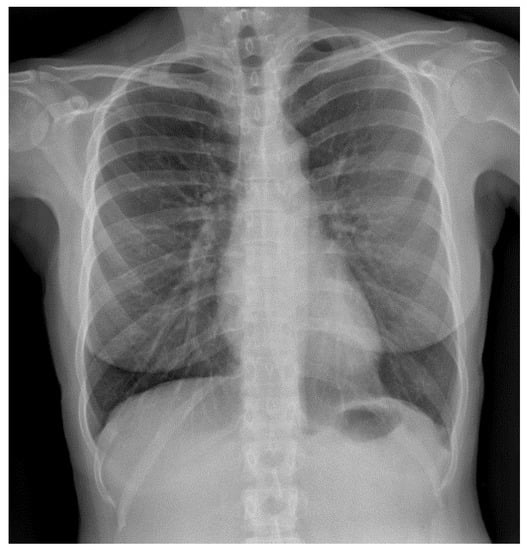

Since lung infections can have multiple causes (not only COVID-19), it is necessary to endow the model with the ability to distinguish COVID-19 infections from other illnesses. Hence, it was necessary to include cases of other possible conditions within the training and testing sets. Great effort was made to obtain as many good-quality images as possible of various types of pathologies. Figure 1 and Figure 2 illustrate samples of pulmonary radiographies of uninfected and COVID-19-infected patients, respectively.

Figure 1. Pulmonary radiography of an uninfected person.